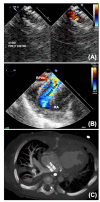

Hypoplastic left heart syndrome (HLHS) is a spectrum of left heart underdevelopment leaving the left side unable to support the systemic circulation. If active management is pursued, then the condition is managed with staged palliation to the Fontan circulation, leaving a systemic right ventricle. Through all surgical stages, and even after completion of Fontan, there are multiple areas that may require intervention, most frequently the branch pulmonary arteries which are essential to a successful Fontan circulation. Echocardiography is the mainstay of assessment, but there is an increasing use of magnetic resonance imaging (MRI) and computed tomography (CT) particularly in relation to extracardiac structures which can be more challenging with echocardiography. Both MRI and CT require set-up, experience and training, and usually sedation or anesthetic in smaller children, but can provide excellent imaging to guide interventions. Cardiac MRI is also able to quantify right ventricular (RV) function which can be challenging on echocardiography. This article describes the modalities available and their use in assessing patients with HLHS prior to catheter interventions.